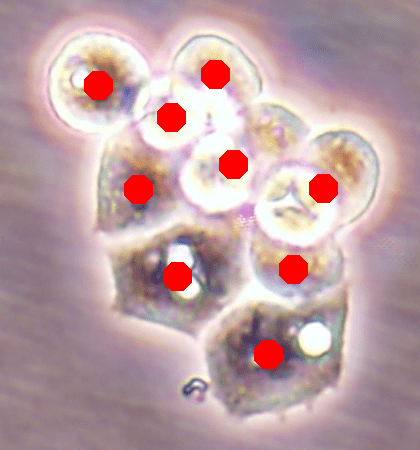

Since the main goal of this work is cell detection, our DeepDistance models define the estimation of an inner distance map as the main task and find regional maxima on this estimated map to detect cells. The motivation behind these choices is the fact that the inner distance definition gives sharp increases at cell centers and the locations with these sharp increases can be detected by finding regional maxima. Hence, to obtain accurate detections, one should estimate an inner distance map with distinct differences between the cell centers and their surrounding pixels such that these centers can be identified as regional maxima. That is, one should estimate a map consisting of sharp enough bright regions close to the cell centers. To improve the performance of the task of this inner distance estimation, our models take advantage of multi-task learning approach. This approach helps the models become more robust to avoid overfitting a task, compared to the approach of learning the same task alone with a single-task model (Caruana, 1997). To get more insight in this multi-task learning approach, this section visually analyzes the estimated maps of single-task and multi-task models.

![]() |

| (a) | (b) | (c) | (d) |

For the independent test samples given in Fig. 4, Fig. 6a shows the maps of the calculated inner distances when the ground truths are given. Figs. 6b, 6c, and 6d illustrate the inner distance maps estimated by the SingleInner method, the proposed DeepDistance model, and its extended version, respectively. SingleInner learns its map as a single-task whereas our models define auxiliary tasks and learn the inner distance map in parallel to these auxiliary tasks, forcing them to learn shared representations with a shared encoder path. The latter type of learning, which is an example of multi-task learning, is known to be effective for increasing the performance of individual tasks for many domains. We also observe this performance increase in the estimated maps given in Fig. 6. SingleInner cannot successfully detect the three cells shown inside red ellipses since it cannot produce sharp enough bright regions (with distinct enough estimated distances) for these cells. Although DeepDistance, which uses one auxiliary task, leads to brighter regions for these cells, they are still not sharp enough for two of them to be identified as regional maxima. The extended version of DeepDistance, which uses one more auxiliary task, does better job in inner distance estimations such that they have sharp enough bright regions for all of these three cells.

In this figure, it is worth to noting two points: First, all methods apply the h-maxima transform on their estimated maps beforehand to suppress noise, and hence, to prevent over-segmentations and false positives. If it was not applied, SingleInner might give regional maxima for some of the three cells even though the distances estimated for their centers were not that distinct (bright). However, that case would also give many over-segmented cells and false positives. Second, none of the methods identify the cell shown inside a blue ellipse although their estimated distances yield bright regions for this cell. It is due to the evaluation method, which matches an annotated marker and a detected cell based on the distance between them since a test set image does not have boundary annotations but just a dot on each cell. In our experiments, a distance threshold is set to 30, considering image resolutions and the average cell size. This threshold may give a few incorrect matchings especially for larger cells, (e.g., the cell shown inside the blue ellipse). Increasing this threshold solves the problem for this particular cell, but this time, it will result in many incorrect matchings of detected cells with distant markers (or vice versa).